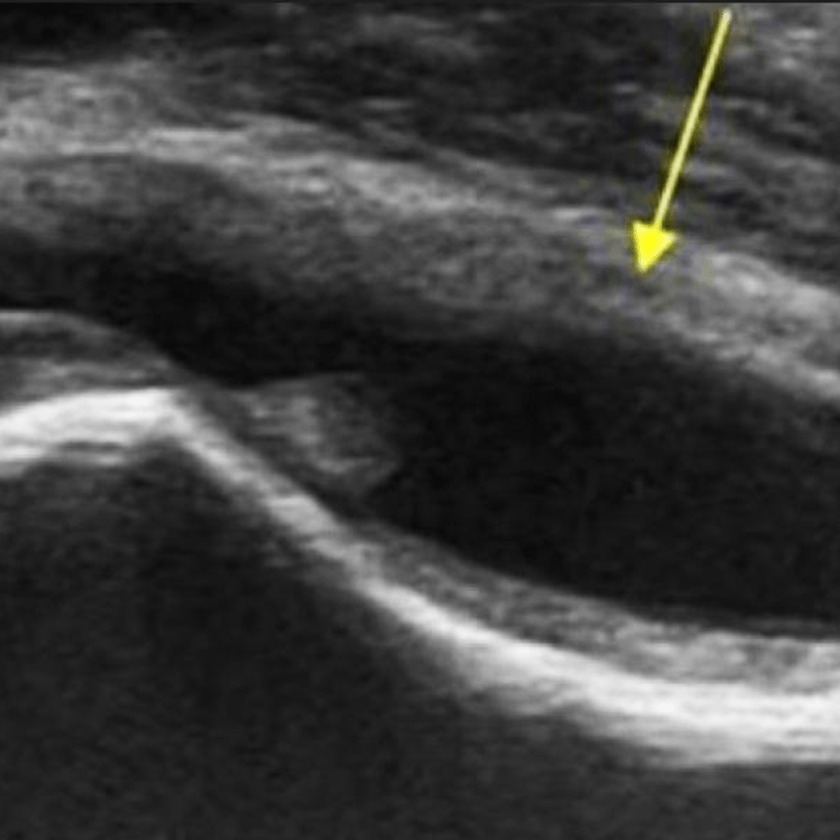

Diagnosticul este stabilit prin examinare clinică, urmată de ecografie pentru a detecta acumularea de lichid în articulație.